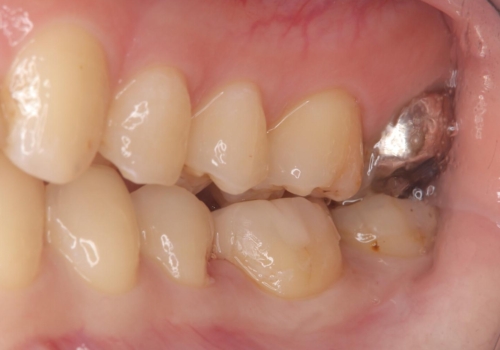

- 主訴:銀の詰め物が取れた、奥の銀の詰め物も一緒に白くしたい

保険適用のメタルインレーの脱離で来院されました。審美性、適合性、清掃性の観点から2本ともセラミックインレーでのやり替えとなりました。

保険適用のメタルインレーはセラミックやゴールドに比べるとプラークなどの汚れが付きやすく、また今回はそこまで大きなう蝕は広がっていませんでしたが、適合性に限界があるためインレーと歯質との境目で二次う蝕が発生する可能性が高くなります。